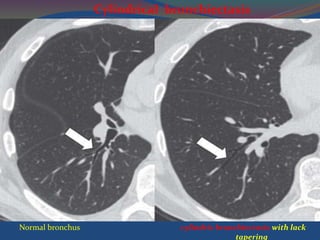

Cylindric Bronchiectasis

 Diagnostic criteria bronchial diameter >

accompanying artery (signet ring sign)

 Lack of bronchial tapering.

signet ring sign

Normal bronchus cylindric bronchiectasis with lack

tapering

Normal bronchus cylindricbronchiectasis with lack tapering Cylindrical bronchiectasis